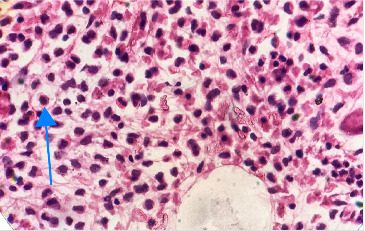

毛细胞白血病(HCL)是一组成熟淋巴样b细胞疾病,其特征是毛细胞的鉴定和独特的遗传谱。流式细胞术检测CD103的表达是计算HCL免疫评分的关键。对于一种在白种人中更为普遍而在非洲人群中较少见的疾病,我们报告了一例罕见的cd103阴性经典HCL病例,患者为43岁的非洲男性,表现为难治性贫血、血小板减少症和脾大。对于难治性贫血患者,考虑调查HCL是至关重要的,因为这可能影响治疗决策,从而影响患者的总体预后。

Hairy cell leukemia (HCL) is among a group of mature lymphoid B-cell disorders characterized by the identification of hairy cells and a unique genetic profile. Detection of CD103 expression on flow cytometry is the key in enumerating the immunologic score for diagnosing HCL. For a disease that is more prevalent in Caucasians and less common in African populations, we report an unusual case of CD103-negative classical HCL in a 43-year-old African male, who presented with refractory anemia, thrombocytopenia, and splenomegaly. In patients with refractory anemia, it is crucial to consider investigating HCL, as this may influence therapeutic decisions and, consequently, overall patient outcomes.